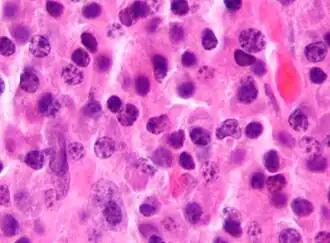

Гемобластозы (лат. haemoblastosis; др.-греч. αἷμα «кровь» + βλαστός росток, зародыш + -osis) — опухолевые (неопластические) заболевания кроветворной и лимфатической ткани.

Гемобластозы подразделяют на системные заболевания — лейкозы, а также регионарные — лимфомы.

Многочисленные работы по изучению морфологии и клеточной кинетики гемобластозов (в первую очередь лейкозов) показали, что при их развитии происходит не только малигнизация на уровне стволовых и полустволовых клеток-предшественниц, но также развивается блок дифференцировки в пуле опухолевых клеток.